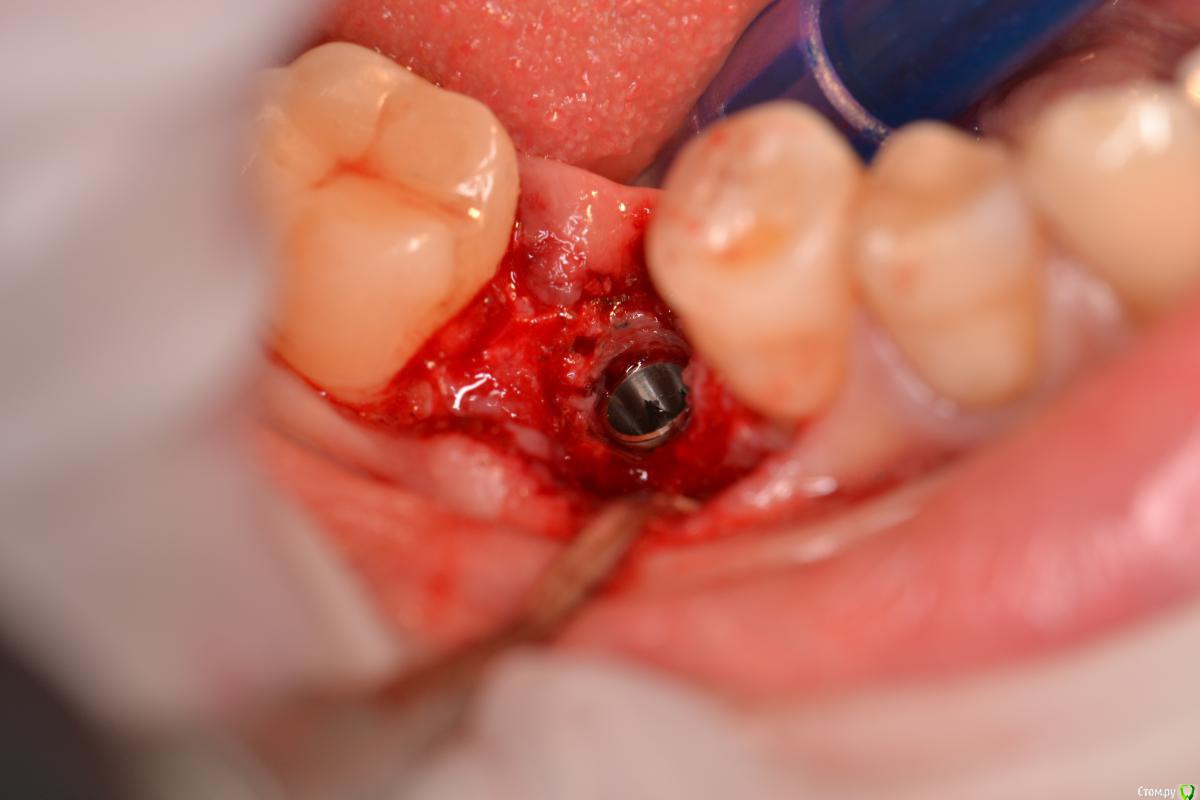

TIGER Опубликовано 22 декабря, 2016 Поделиться Опубликовано 22 декабря, 2016 Если вам сегодня нравится,что вы сделали вчера ,то вы стоите на месте....)Имплант ставил я, с виду по первому фото видно,что вроде-бы ничего...но на тот момент я бы был удовлетворён результатом,да он интегрирован,пациент доволен,отпротезировал бы,но сегодня нет...зондирование выявило резорбцию....и главное я знал,что прогноз не очень,эстетика и жизнь этого болтика...настоял на удалении...сегодня заказал набор,и на выход,сразу же имплант,заглубил,как надо)Как говорил если мне не изменяет память Эдуард Анчаков наступает эра вынимайзинга....начал со своего)P.S какое приятное чувство когда ты можешь исправить свои недочёты) 3 Ссылка на комментарий

TIGER Опубликовано 22 декабря, 2016 Автор Поделиться Опубликовано 22 декабря, 2016 Почему такое могло произойти,есть снимки после установки?Недозаглубил...банально...Снимка нет Ссылка на комментарий

Тимур86 Опубликовано 23 декабря, 2016 Поделиться Опубликовано 23 декабря, 2016 как недозаглубление вызывает такую сильную резорбцию? 5 Ссылка на комментарий

TIGER Опубликовано 24 декабря, 2016 Автор Поделиться Опубликовано 24 декабря, 2016 как недозаглубление вызывает такую сильную резорбцию?несколько факторов в купе... Ссылка на комментарий